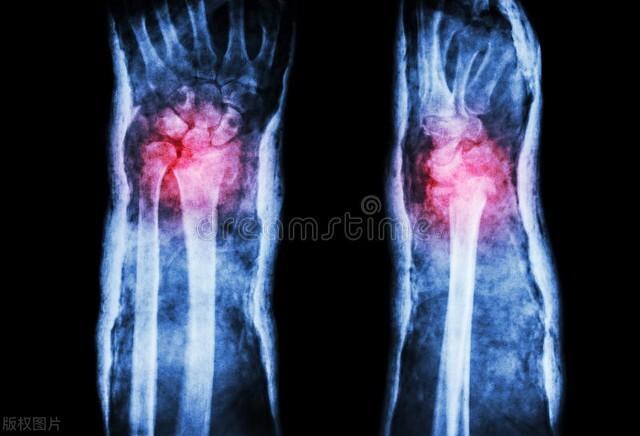

其次,碳酸飲料也是傷害骨骼的“元兇”之一。碳酸飲料,那充滿氣泡的甜蜜誘惑,對於許多人來說是難以抗拒的。然而,它就像是一場“酸雨”,無情地衝刷着我們骨骼這座寶貴的“森林”。

碳酸飲料中的磷酸成分,就像一把銳利的斧頭,不斷砍斷骨骼中鈣吸收的通道。鈣,作爲滋養骨骼森林中樹木的重要土壤,因爲磷酸的存在而無法被充分吸收和利用,與此同時,碳酸飲料中大量的糖分不僅容易導致肥胖,還會給骨骼增加額外的負擔。想象一下,肥胖的身體就如同給骨骼森林壓上了沉重的巨石,樹木(骨骼)在重壓之下難以挺直生長。